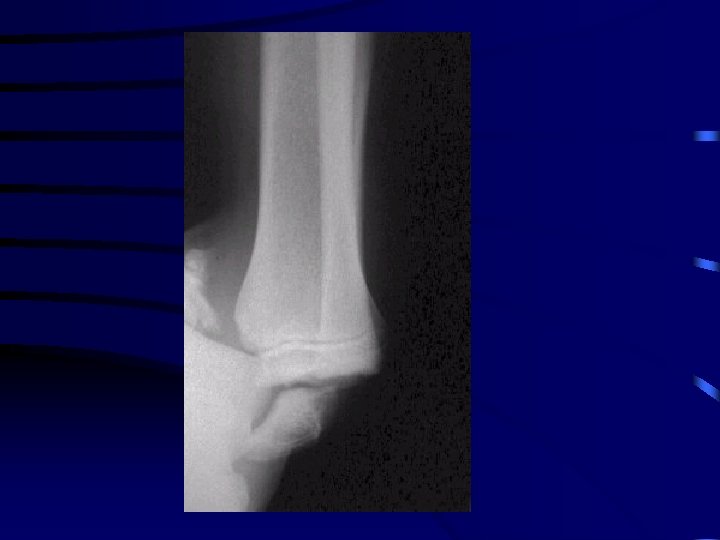

Particularité : le coude • L'examen clinique doit recher : · une atteinte nerveuse : médian (et en particulier l'atteinte du nerf inter-osseux antérieur), radial ou ulnaire · une atteinte vasculaire : recherche du pouls radial • Bilan radio : radiographie du coude Face et Profil

Recherche épanchement